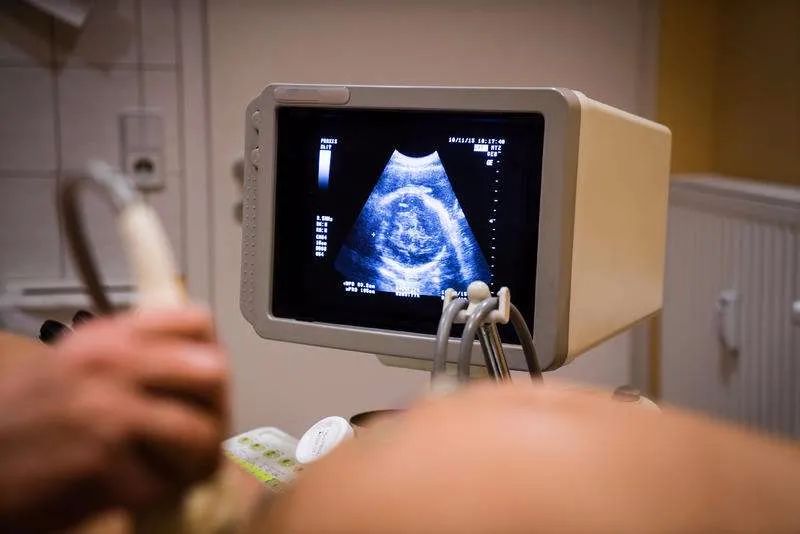

如果整个孕期胎儿发育比较正常,孕妈没有妊娠并发症,也没有特殊的疾病,胎儿也没有出现缺氧或者羊水过少、胎心变化等,建议到孕39周以后再进行剖腹产,相对来说这个是最合适的时间。因为这个时候胎儿已经足月,身体的各项指标已经发育成熟,也具备了存活的条件。

如果没有异常的情况下,孕妇最好不要在怀孕39周前做剖腹产,以避免婴儿出现严重并发症,尤其是呼吸系统疾病。因为胎儿的肺脏是最后成熟的器官。

如果是疤痕子宫、胎位不正、骨盆狭窄、妊娠期糖尿病或者双胎等情况是可以择期剖宫产的。但是最好要等到孕37周以后,保证安全的前提下能坚持到38周更好。如果孕周太小,胎儿还未成熟,分娩后护理会相对困难。如果孕周太大,尤其是有疤痕子宫者引起先兆子宫破裂甚至子宫破裂以及胎儿窘迫的风险会增大。